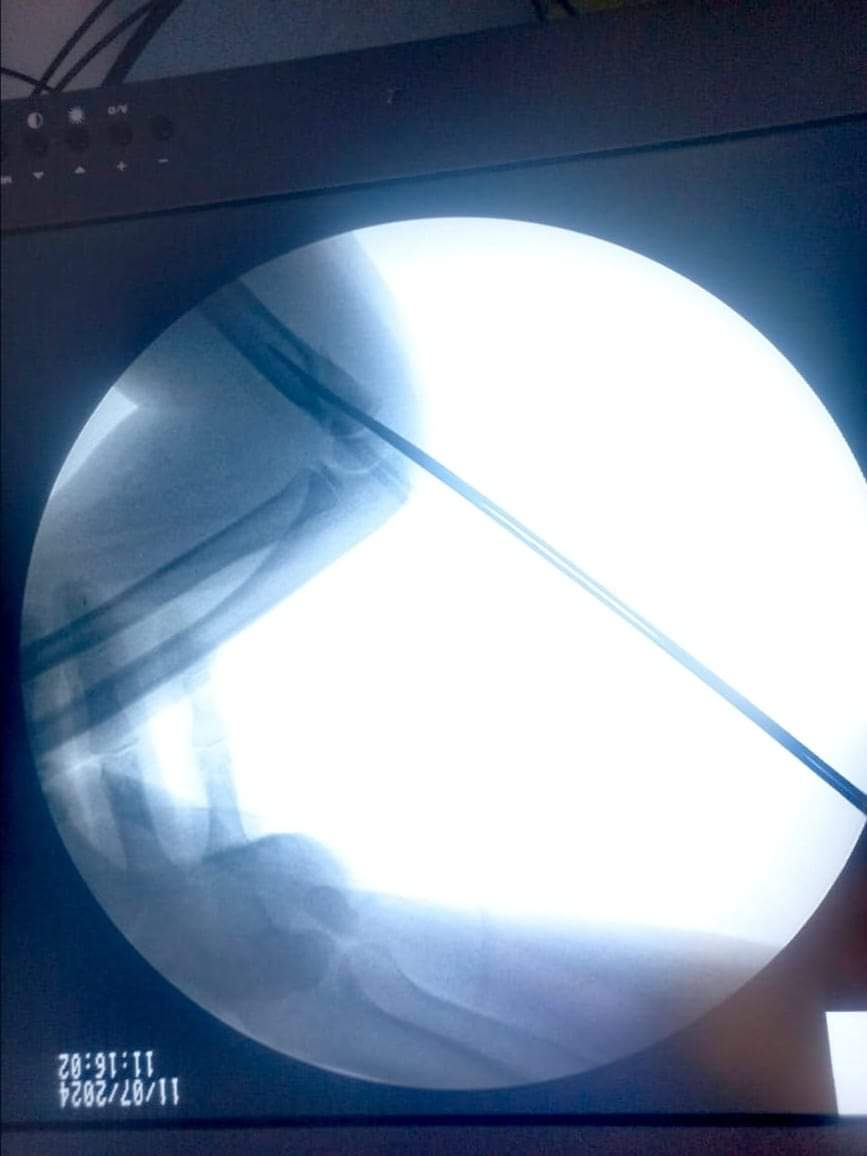

وطنا اليوم -  يقوم بعمليات تثبيت الكسور المعقدة بشكل طاريء وتبديل المفاصل بشكل مبرمج  مما خفف على المواطنين البحث عن أسرة في مستشفيات مركزية رغم صعوبة عمليات العظام من الناحية التقنية في المستشفيات النائية  إضافة الى  استقبال اعداد كبيرة بالعيادات ومعالجة جميع المرضى بالطرق المثلى انه الدكتور الانسان البارع والمتميز يزيد البريزات طبيب العظام في مستشفى الاميرة سلمى / ذيبان عيادة العظام  علماً بأنه كان  مستشفى تحويلي منذ تاسيسه والدكتور البربزات وقبل اربع سنوات في عام 2020  منذ انتقاله للمستشفى يقوم بهذه العمليات ومن بينها  عمليات نوعية لمرضى يعانون من كسور معقدة في الترقوة واجراء عمليات دقيقة ومعقدة لكسور لمرضى في مختلف أنحاء الجسم وعمليات تثبيت الكسور المعقدة وتركيب المفاصل وغيرها الكثير  والديسك " وآلامه وتبعاته وعلاجه وإجراء عمليات معقده وصعبه.

وأجرى الدكتور البريزات عمليات كبرى في جراحة العظام والتي تحتاج إلى مراكز متقدمة ومتطورة. وكذلك العمل على تثبيت أغلب انواع الكسور بطريقة طارئة وتبديل المفاصل بطريقة مبرمجة بما يتناسب مع امكانات المستشفى والتي هي  جزء من  العمليات الدورية بمستشفى الاميرة سلمى في ذيبان  والتي تخفف العبئ على المستشفيات المركزية وعلى المواطن في آن واحد.

وعبر كثير من  المرضى وذويهم عن عظيم شكر هم وامتنانهم للدكتور البريزات على ما بذله ويبذله  من جهود كبيرة واستثنائية في تعامله مع المرضى والمراجعين  ومتابعته الحثيثة لهم والاطمئنان عليهم والتي تكللت جميعها بالنجاح وله الدور الكبير   برفع كفاءة قسم العظام  بالمستشفى بشكل عام والذي  أصبح  متطوراً بالقيام بالعمليات مثل تثبيت الكسور المعقدة و تركيب المفاصل و غيرها.